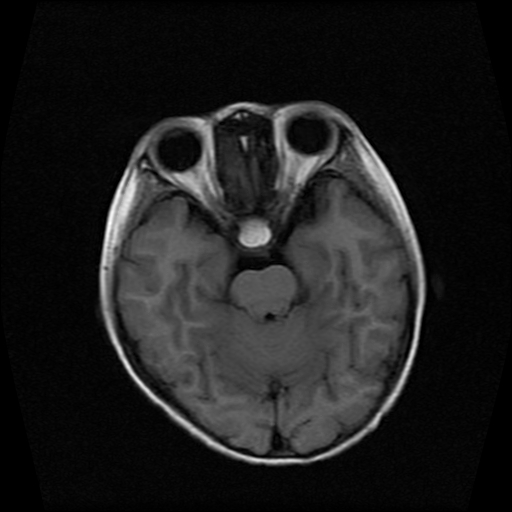

男性,12岁。反复头痛呕吐半月。脑积液无异常。病变部位ct值32hu,dwi无异常。

鞍上为主,累及鞍内,垂体受压位于鞍底。mri呈短t1、长t2信号,不太支持生殖细胞肿瘤,首考颅咽管瘤。

鞍内囊性占位性病变,t1wi、t2wi,均为高信号影。ct平扫为等密度。发病年龄较小。故首先考虑颅咽管瘤,可以做ct增强扫描

鞍内囊性占位性病变,t1wi、t2wi,均为高信号影。ct平扫为等密度。发病年龄较小。故首先考虑颅咽管瘤。